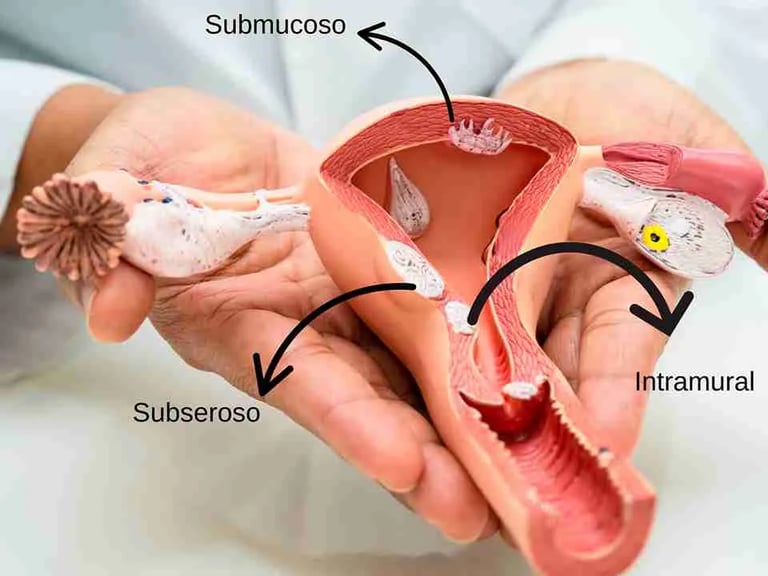

Embolização de mioma uterino

Ablação de miomas uterinos